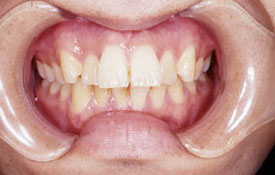

インビザラインの治療例:CASE-2

| プロフィール | 15歳 男性 |

| 所見 | アメリカから転院されて来られた方です。 インビザラインで上下顎の矯正治療を開始し下顎はアメリカで終了しており、上顎のみ治療の後期を担当しました。 アイライナーの装着は、1日平均22時間ほどでした。 |